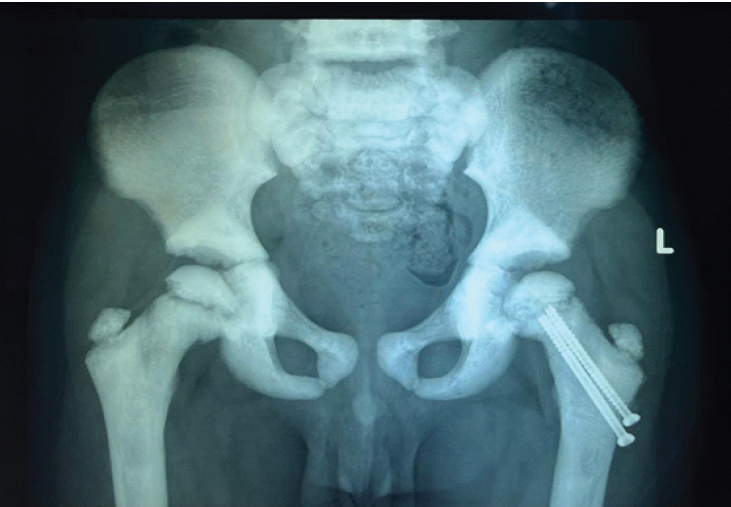

Seven months postoperatively, the child presented with a painless limp and apparent limb shortening. Radiographs revealed slippage of the capital femoral epiphysis despite fracture union (Fig. 5).

Figure 5: Radiograph at 7-month follow-up demonstrating slippage of the capital femoral epiphysis.

The likely cause was stress concentration at the screw tips adjacent to the physis. Revision fixation was deferred due to the small size of the epiphysis and anticipated poor screw purchase. At 1-year follow-up, radiographs demonstrated progression of epiphyseal slippage with significant limb length discrepancy (Fig. 6), although the child remained painless and ambulatory.

Figure 6: One-year post-operative radiograph showing progression of epiphyseal slip with limb length discrepancy.